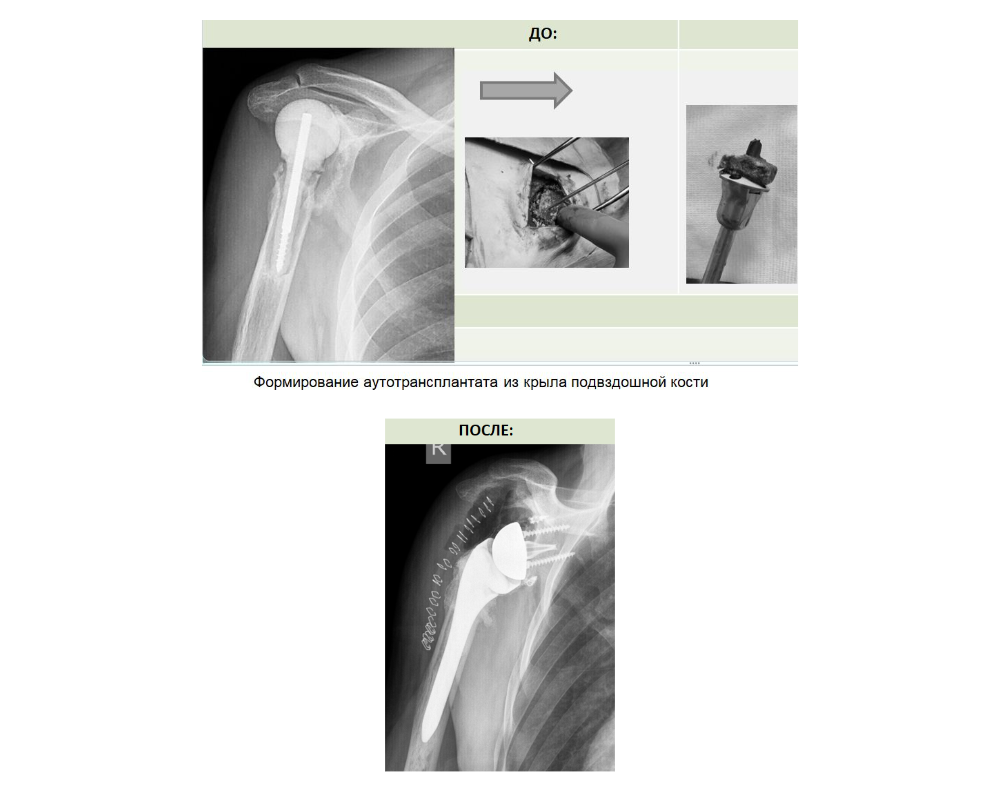

Сложнее, когда головки плеча нет. В таком случае аутотрансплантат формируют из гребня подвздошной кости. Так было в истории с пациентом из ЯНАО.

Молодой мужчина 44 лет получил вывих плеча при падении. Обратился к костоправу, заработал абсцесс. После этого возникло еще и гнойное осложнение. До ликвидации гнойного процесса мужчине установили временный протез. Многочисленные операции по месту жительства были безрезультатны.

Требовалось очередное вмешательство экспертного уровня. Для хирургического лечения травмы плеча в Центре Илизарова провели ревизионное эндопротезирование с костной аутопластикой из гребня подвздошной кости.

Справка: Подвздошная кость — наиболее крупная из трёх костей, формирующих тазовую кость.